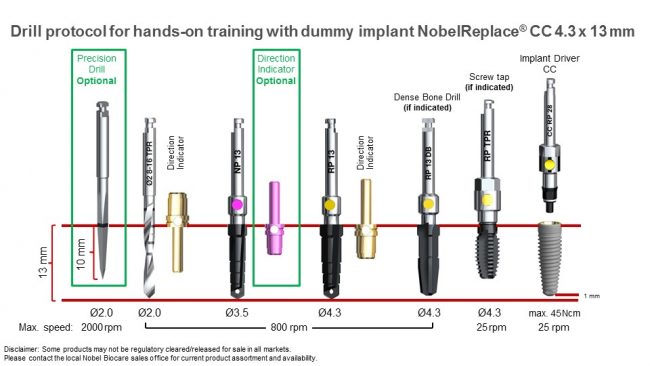

Вновь обращаясь к тезису о полированных частях имплантата, повторюсь, что они должны находиться выше уровня костной ткани. Почему? Всё по тем же причинам, что и с трансгингивальными имплантами: хирургический протокол не предполагает субкрестального погружения субгингивальных имплантатов даже при условии подготовки лунки большей глубины. Например, вот протокол установки Nobel Replace CC 4.3×13:

Это картинка с официальной презентации Nobel Biocare. Ни в ней, ни где-либо еще нет упоминания о возможности субкрестальной установки Nobel Replace CC. Так откуда пошла мода «топить» эти имплантаты глубоко в костную ткань?